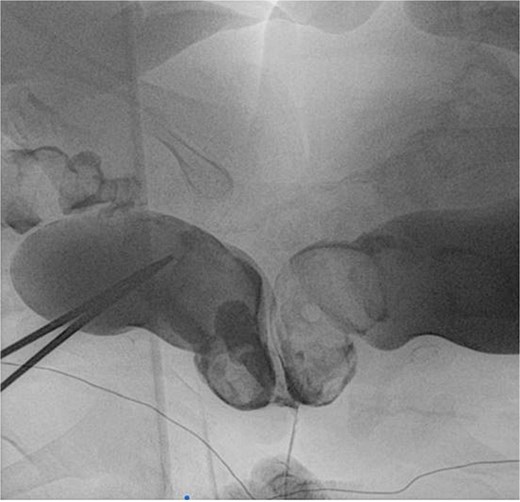

Weighing 15 kg combined, the twins were joined at the sacral region, with partial fusion of hips. Each had a single kidney and separate bladders, with shared ureteral and anal openings, and two vaginal orifices. Twin A was slightly larger and calmer. No spinal cross-connections were noted. Investigations included MRI, angiography, and endoscopic procedures. Imaging revealed fused sacral vertebrae, shared dural sac, tethered cords, and convergence of two rectums into a single anal canal. Vascular anastomoses existed between the internal iliac branches (Figs. 2 and 3).

Rectal contrast filled two separate rectums fused distally to form a single anal canal.